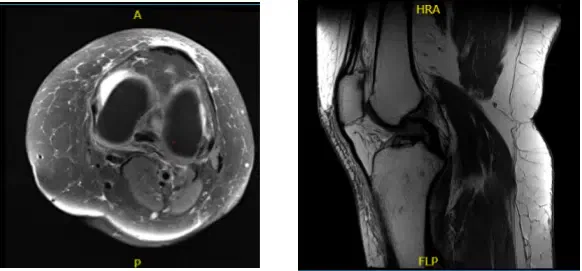

Realizamos una resonancia magnética que reveló una lesión parcial de LCA de alto grado. Ten en cuenta que el paciente era joven, estaba enfermo, y hablamos sobre nuestras alternativas. La rodilla también tenía muy poca artritis. Se exploraron alternativas de tratamiento, incluyendo el conocido manejo quirúrgico.

MRI-3T Rodilla Izquierda sin contraste